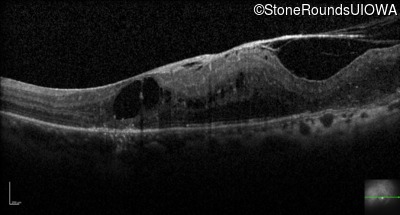

Optical Coherence Tomography - Right - 20/50 -2

Exemplar / OCT Stack

OCT Stack